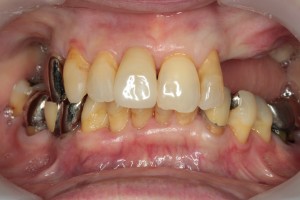

症例⑤

上左右の奥歯を失ってしまったため、保険の入れ歯を入れたが、違和感が強く、しっかり噛むことができないため、インプラントを併用した入れ歯を作ることで違和感なく、しっかり噛むことができるようになった。 また通常の入れ歯は、はずれないようにするため金属のバネを歯に引っ掛けるため見た目も悪いが、インプラントによって固定されているためバネもなく、見た目も非常に良いものとなっている。

術前

術前レントゲン写真

術後レントゲン写真